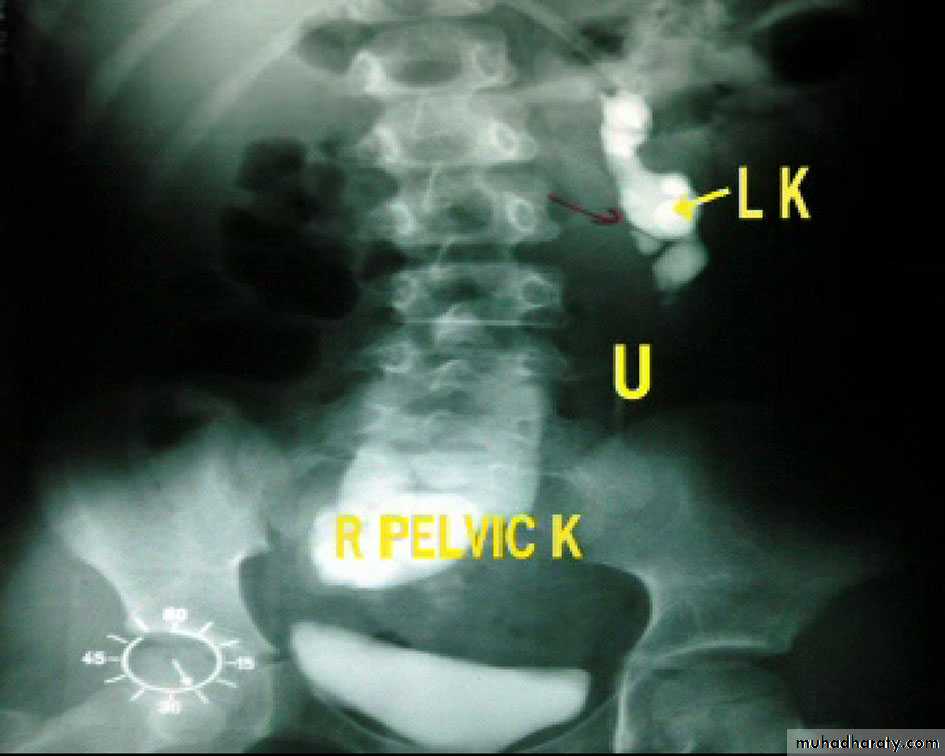

Ectopic kidney:

- Result from halted ascend of kidneys during fetal development

- Often are incidental findings during routine ultrasound, -usually located in the lower abdomen and rotated, -short ureter.

-Chronic pyelonephritis, calculi and hydronephrosis are more common .